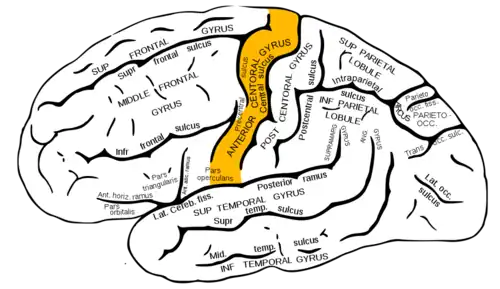

Le gyrus précentral ou circonvolution frontale ascendante est un gyrus de la face latérale du lobe frontal du cortex cérébral, limité en avant par le sillon précentral et en arrière par le sillon central de Rolando.

Cette circonvolution contient le long de la face antérieure du sillon central les aires motrices primaires M1, correspondant à l'aire 4 de Brodmann. Les centres commandant les mouvements musculaires intentionnels sont organisés suivant une carte motrice : chaque partie du cortex M1 commande les muscles d'une partie du corps controlatérale (du côté opposé du corps).